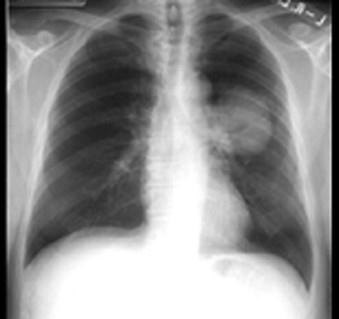

既往健康的68岁男性患者,吸烟40年,因咳嗽,反复肺部感染,于门诊抗炎治疗近1年,胸部X线复查如图所示,形态不规则,边缘不整齐,收入院进 一步检查治疗。 ...

问题 既往健康的68岁男性患者,吸烟40年,因咳嗽,反复肺部感染,于门诊抗炎治疗近1年,胸部X线复查如图所示,形态不规则,边缘不整齐,收入院进 一步检查治疗。 为进一步确诊,首选的检查方法是 ( )

选项 A、开胸探查 B、支气管镜检 C、痰细胞学检查 D、胸腔检查 E、经胸壁穿刺活检

答案 B